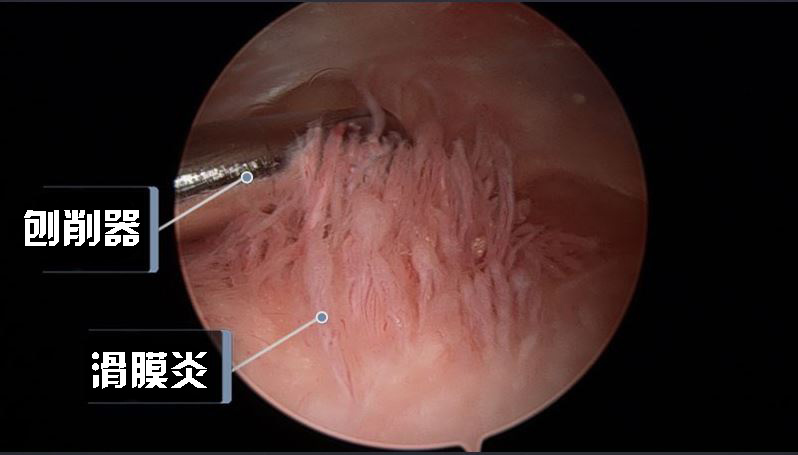

03 / 滑膜切除术

类风湿关节炎的早期,病变场所主要在滑膜,表现为滑膜发炎、充血、肿胀和增殖,没有或者只有轻度的软骨及骨的改变和破坏,但随着病情发展,滑膜的病变可对软骨和骨造成破坏,导致关节畸形。

对于联合使用药物无法控制病情的患者,则需要考虑滑膜切除术。在关节镜探视下切除增生的滑膜组织,可以降低关节腔的压力,缓解疼痛的症状,也可以减少关节积液和炎症物质的释放,防止骨和软骨的进一步破坏,还可以消除增殖滑膜造成的机械性阻碍、对关节伸直的干扰和炎症刺激引起肌肉痉挛、关节屈曲挛缩,有助于关节活动度的改善。

滑膜切除术可帮助患者消除疼痛、缓解骨和软骨的破坏、改善关节功能,适用于膝、肘、肩等大关节,不适合手指小关节。

关节镜下滑膜切除术